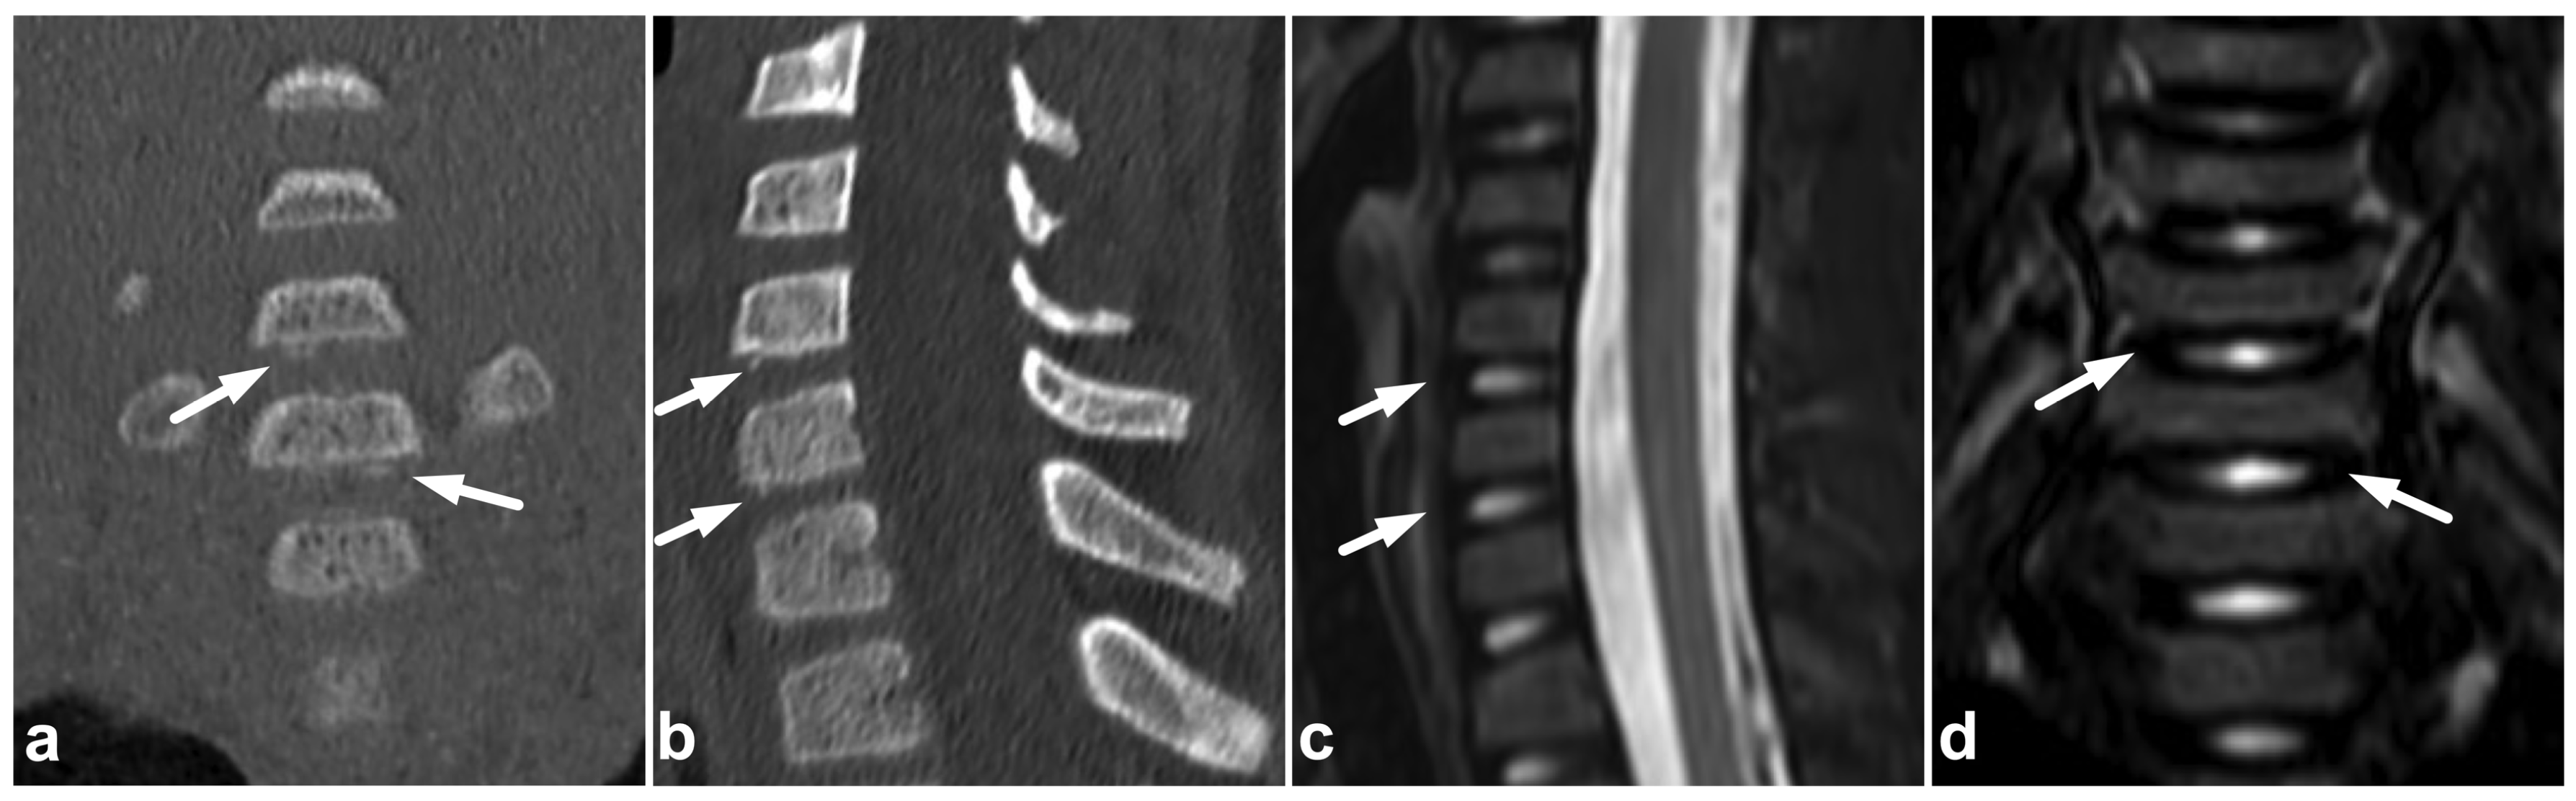

7.3. Juvenile Spondylolysis

7.4. Imaging Appearances of Normal Skeletal Maturation